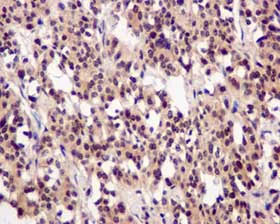

Immunohistochemistry (Formalin/PFA-fixed paraffin-embedded sections) - Anti-PSMC5 antibody [EPR13565(B)] - BSA and Azide free (AB240208)

Immunohistochemical analysis of paraffin-embedded Human thyroid carcinoma tissue labeling PSMC5 with unpurified ab178681 at 1/50 dilution.

This data was developed using the same antibody clone in a different buffer formulation containing PBS, BSA, glycerol, and sodium azide (ab178681).